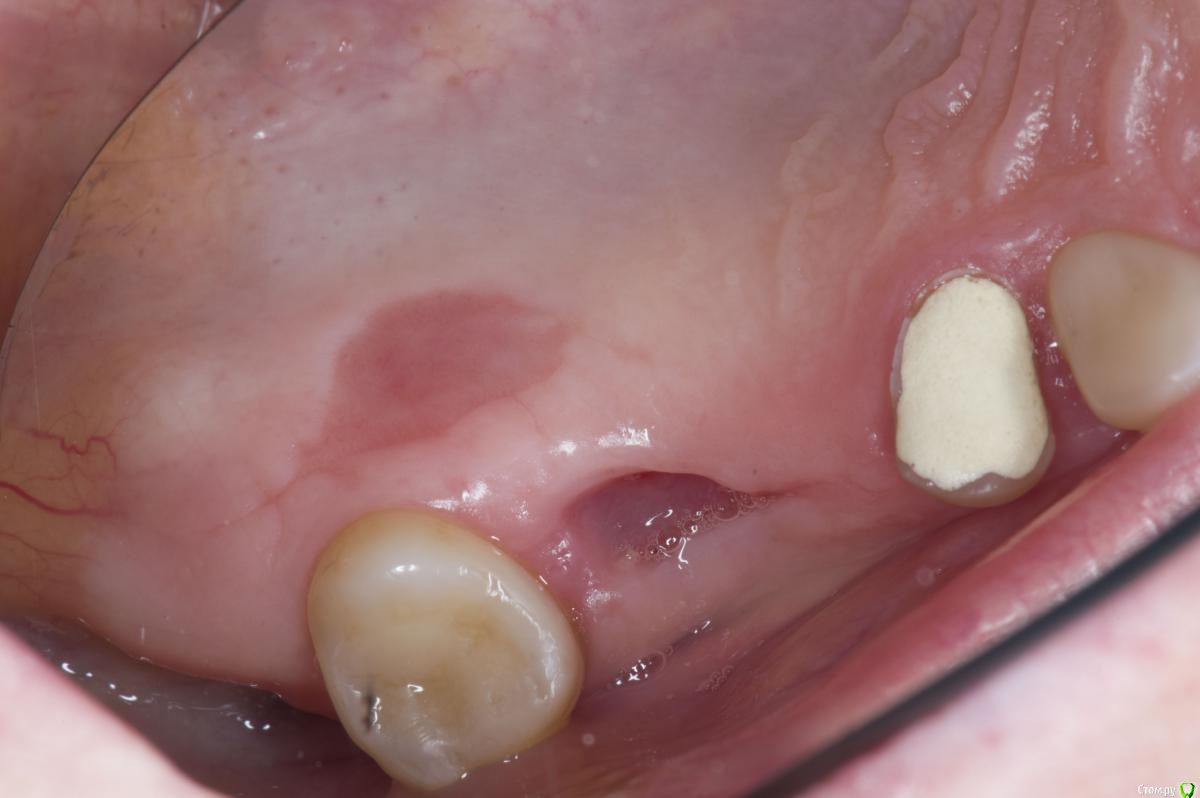

Sampson Опубликовано 13 июля, 2018 Автор Поделиться Опубликовано 13 июля, 2018 Вид через 7 дней.Не болит, нет отека.Швы на 45 46 тугие.при подтягивании безболененые и кровоточат. Ссылка на комментарий